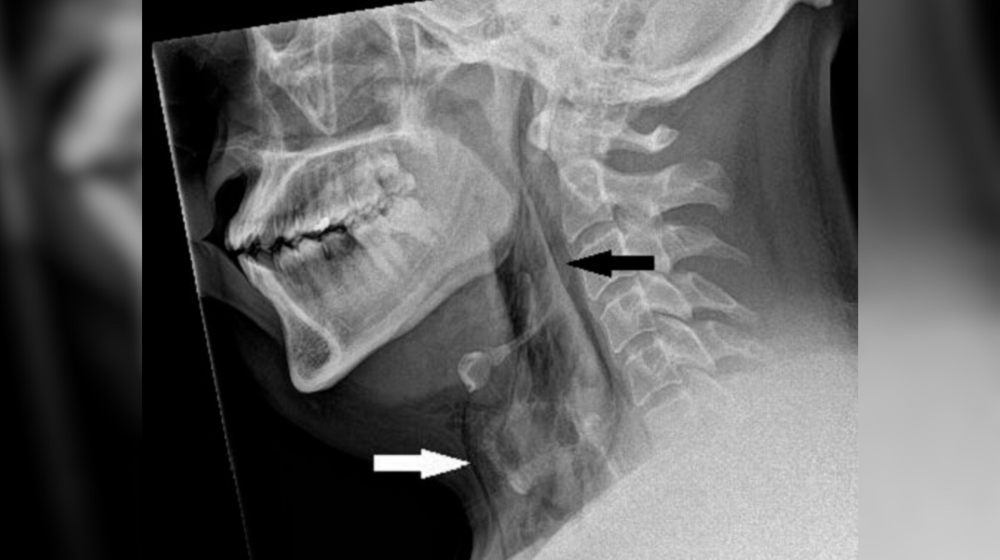

Хотя у пациента не было проблем с дыханием или речью, при осмотре медики услышали характерный хрустящий звук — крепитацию. Рентген показал наличие подкожной эмфиземы — скопления воздуха в глубоких тканях. Дальнейшая КТ подтвердила разрыв трахеи между третьим и четвертым шейными позвонками. Размер отверстия составил всего 2×2 мм, но этого хватило, чтобы воздух начал проникать в окружающие ткани и средостение.

"Резкий скачок давления в дыхательных путях при подавленном чихании — вот что привело к разрыву", — заключили врачи.